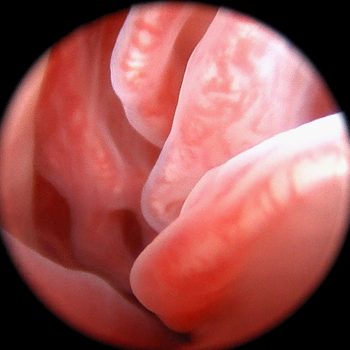

Diagnostyka endoskopowa układu oddechowego (laryngoskopia, tracheoskopia, bronchoskopia)

Zalecana w przypadku:

Przewlekłego lub napadowego kaszlu

Trudności w oddychaniu

Świszczącego lub chrapiącego oddechu

Objawów zespołu ras brachycefalicznych

Podejrzenia ciała obcego

Krwawienia z dróg oddechowych

Przewlekłych infekcji układu oddechowego

Leczenie:

Porażenia krtani u psów i kotów (metoda endoskopowa przy użyciu lasera)

Badania dodatkowe:

Pobieranie popłuczyn oskrzelowo-pęcherzykowych

Cytologia

Wymazy

Biopsja